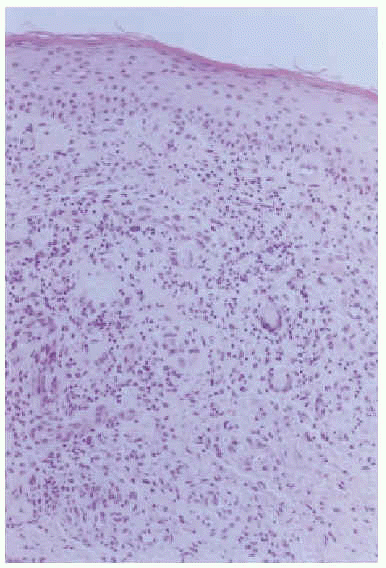

Una mujer de 67 años, con síndrome mielodisplásico (anemia refractaria con exceso de blastos) que había evolucionado a una leucemia aguda no linfoblástica de tipo M5 de la FAB, consultó por neutropenia y fiebre. Se inició tratamiento empírico con ceftacidima, amikacina, vancomicina, anfotericina B y G-CSF en dosis de 300 mg/día, por vía subcutánea, por una leucopenia grave. Cinco días después de comenzar el tratamiento con G-CSF la paciente desarrolló un exantema diseminado de aspecto polimorfo, localizado en el tronco y las extremidades. Estaba formado por áreas morbiliformes, asociadas con elementos purpúricos y liquenoides (fig. 1). El estudio histopatológico mostró un infiltrado de aspecto granulomatoso en la dermis papilar (fig. 2) formado por histiocitos, células gigantes multinucleadas, neutrófilos, eosinófilos, linfocitos y ocasionales células plasmáticas (fig. 3). La epidermis y la unión dermoepidérmica no presentaban alteraciones. Las tinciones con reacción del ácido peryódico de Schiff (PAS) y Ziehl-Nielsen fueron negativas. El estudio inmunohistoquímico demostró una moderada positividad para CD68 en las células de las estructuras granulomatosas.

Fig. 2.--Panorámica del estudio histológico donde se observa la ocupación de toda la dermis por un infiltrado de aspecto granulomatoso.